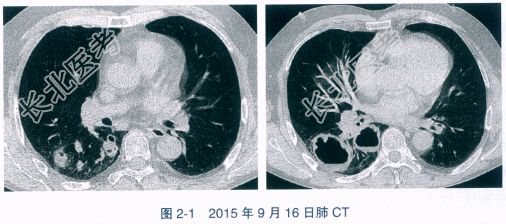

10pg/ml。GM试验阴性。抗核抗体(antinuclear antibody,ANA)阴性,自身抗体谱14项:阴性。抗中性粒细胞胞浆抗体(antineutrophil cytoplasmic antibody,ANCA)阴性,抗蛋白酶3(proteinase 3,PR3)抗体阴性,抗髓过氧化物酶(myeloperoxidase,MPO)抗体阴性。IgG:641mg/dl。肺CT:右肺下叶可见多个大小不等的肿块、结节,大部分病变内部可见空洞,洞壁厚薄不均匀,并可见壁结节,部分洞内可见气液平面(图2-1)。